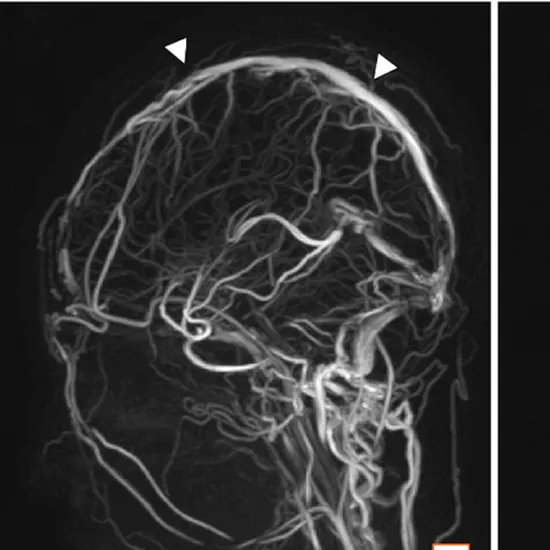

While doing magnetic resonance venography (MRV) to get clarity of images the contrast is injected into the brain.

MRV with contrast dye makes the blood vessels seem dense on the X-ray picture, helping the doctor to see the blood vessels under examination.

In the MRV process the combination of large magnets and radio waves are utilized creating the imaging. To get more depth and clarity of the images a intravenous contrast dye is injected during the scan.